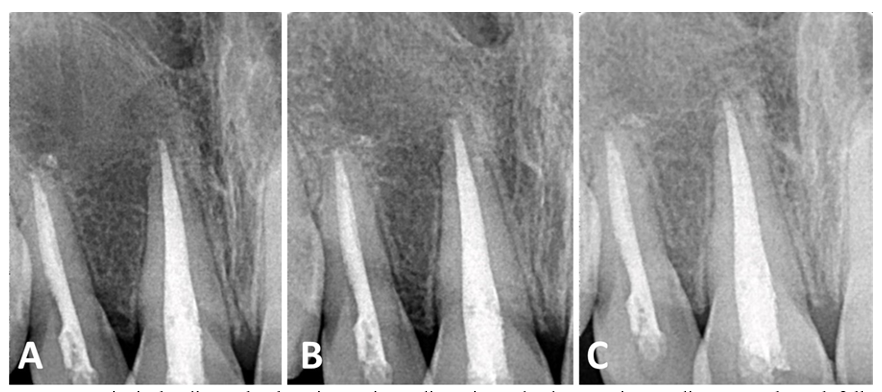

The patient did not report any painful symptoms during the 3-month rest treatment or at other follow-up visits. The case was clinically asymptomatic as all signs and symptoms had disappeared completely, and the gingiva appeared normal on follow‐up recall (Figure 3). Periapical radiographs show signs of healing of the periapical lesion, increasing radiopacity, and decreasing root divergence through follow‐up recall at 6, 12, and 18 months (Figure 4).

Figure 3 Clinical lateral views show the straightening of the tilted lateral incisor #12 (arrow) after two years (A) and complete treatment after restoration of the upper central incisor #11 (B).